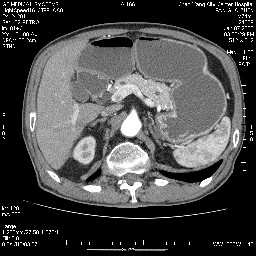

女,74岁,呕吐10余日

壶腹部的占位性病变,考虑为十二指肠癌并梗阻,但脾内多发性低密度区为转移吗?

还有胃、脾之间可见有侧支循环建立。左肾盂积水。

肝胰壶腹占位,考虑-壶腹癌!

胃体部粘膜不规则增厚,胃肠造影也显示充盈缺损-胃溃疡?胃癌?

双肾多发小囊肿;左肾积水。

十二指肠降段扩张,水平段狭窄成鼠尾状,肠壁明显增厚,胰腺勾突增大成不均匀强化,其内可见低密度区,胆囊增大,1十二指肠水平段腺癌侵犯胰腺勾突可能大,2胰腺癌侵犯十二指肠(只有胆囊增大没有肝内外胆管扩张不好解释)代除外.

上消化道造影见十二指肠结节状充盈缺损,ct增强十二指肠壁局限性增厚并强化,考虑十二指肠壶腹癌?

十二指肠降段扩张,水平段狭窄成鼠尾状,肠壁明显增厚,胰腺勾突增大成不均匀强化,其内可见低密度区,胆囊增大,1十二指肠水平段腺癌侵犯胰腺勾突可能大,2胰腺癌侵犯十二指肠 。

今日手术结果:胰腺钩突癌侵犯十二直肠,腹腔淋巴结转移.